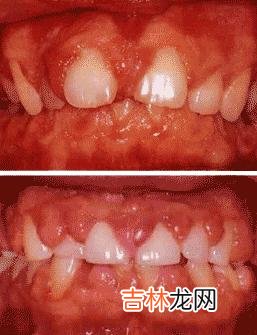

【最常见的龈炎是哪种能够预防吗】 在龈炎中最常见,也最易发生的是慢性单纯性龈炎,又称为边缘性牙龈炎或龈缘炎 。几乎每个成年人在其一生中的某一个时期均可能发生程度不同、范围不等的慢性龈炎 。它是以长期堆积在龈缘处牙面上的菌斑为始动因子的 。牙石、不良修复体、食物嵌塞、口呼吸等因素可以加重菌斑的堆积,加重牙龈的炎症 。

一般轻度的单纯性龈炎只侵犯游离龈和龈乳头,严重者可波及附着龈 。患处牙龈瘀血发红,水肿光亮而松软 。龈缘变厚而不贴附于牙面 。牙间乳头变得圆钝、肥大 。牙龈被触碰、刷牙、咬物时流血 。甚者龈缘糜烂或有肉芽增生、龈袋溢脓,龈沟可由于肿胀而变深,超过3mm,其龈沟底仍位于釉牙骨质界的冠方 。x线片示齿槽骨无明显吸收 。

除去病因后数日至1周内即可治愈 。可行洁治术彻底清牙石,控制菌斑,改正一切造成菌斑滞留和刺激牙龈因素,如矫正不良的修复体及食物嵌塞,充填邻面龋,调牙合等 。教会患者正确的刷牙方法,饭后漱口 。局部涂碘甘油等药物以消除炎症 。

慢性单纯性龈炎是能够预防的,其关键在于坚持每天彻底地清除牙菌斑,即每天用正确地刷牙方式早晚刷牙,使用牙线和牙签清除牙齿邻面菌斑和食物嵌塞等 。